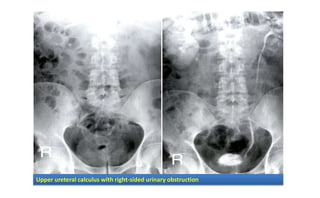

Diagnosis: Imaging

• Rarely used :

– KUB :

• Can not detect hydronephrosis

• Miss small and radiolucent stones

– IV Pyelogram

• Most useful test for defining degree and extent of urinary tract

obstruction

• This is usually not necessary for the diagnosis of renal calculi.

Upper ureteral calculus with right-sided urinary obstruction